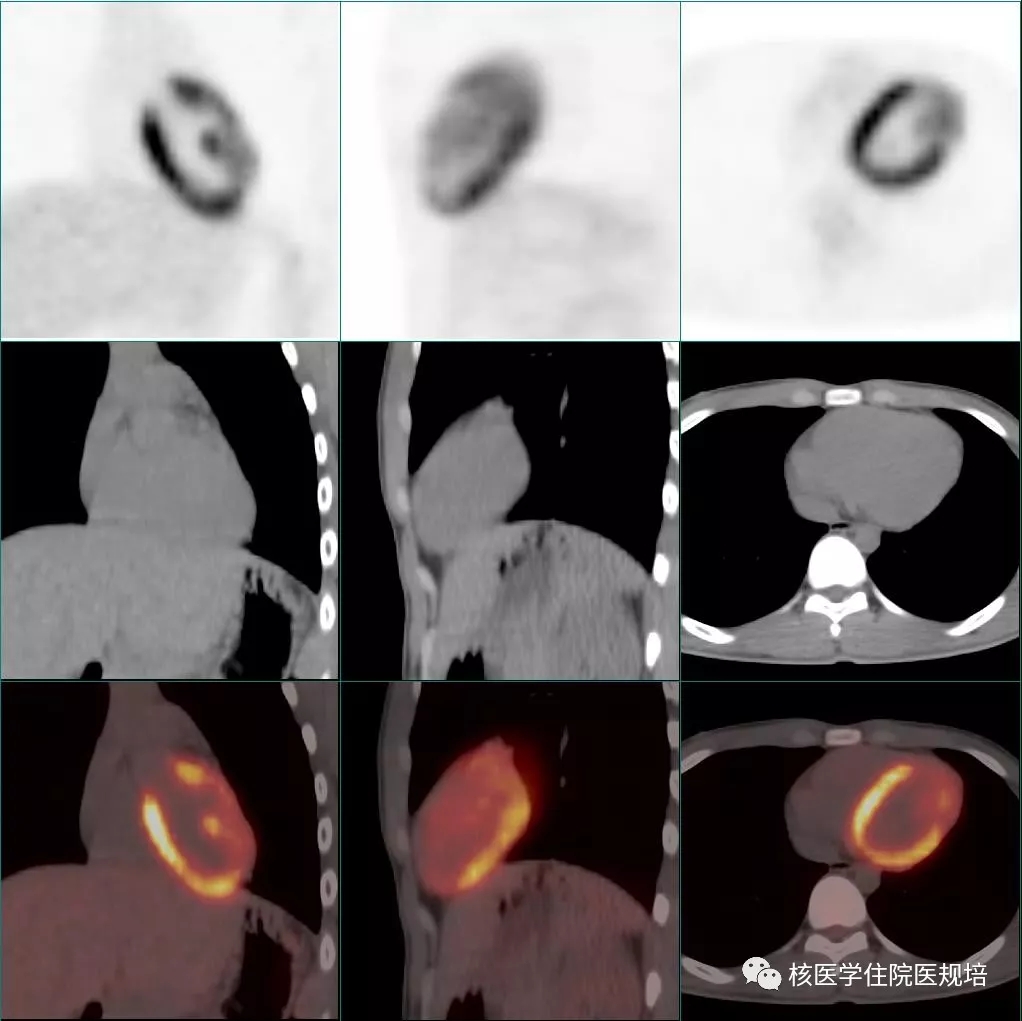

隔日再次行胸部 FDG PET/CT显像。显像前连续两餐进食低碳水化合物、高脂食物(第一餐为2只猪手,第二餐为5个茶叶蛋),第二餐4h后开始显像。与前次显像对照,除肿物显影外,左室其余心肌未见明显FDG摄取;前侧壁至心尖处占位表现为FDG摄取增高灶(SUVmax5.3),边界较清晰,范围约4.0×2.8×4.5cm,并侵犯乳头肌(图7)。

图7